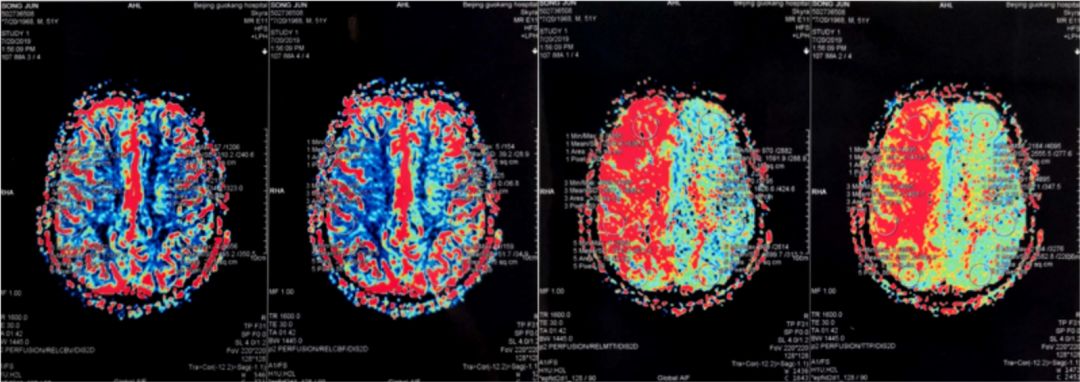

2019-07-20外院PWI:右侧额颞叶灌注信号减低(图4)。

图4